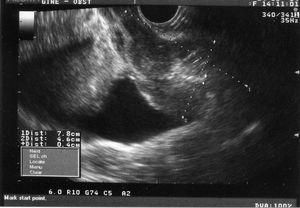

En la exploración encontramos un himen íntegro, abundante material hematicopurulento y una tumoración friable, sangrante al contacto, que afecta a todo el fondo de saco lateral derecho y que llega al tercio inferior de la vagina. El cérvix es imposible de visualizar y, al tacto, es irregular y duro. Ecográficamente, encontramos un útero de 8 * 4,6 cm, ecomixto, con un endometrio de 4 mm, y los ovarios son normales (fig. 1). La paciente es ingresada para su estudio.

Fig. 1. Ecografía transrectal, corte longitudinal: útero en retro regular de 7,8*4,6 cm de ecogenicidad heterogénea con endometrio atrófico.